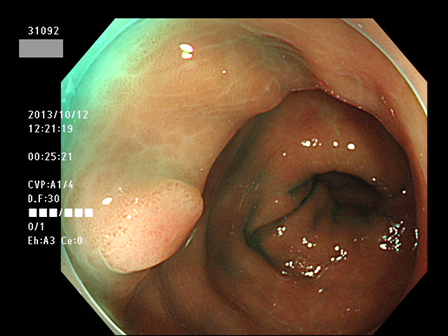

上記100名より抽出した平坦・陥凹型腺腫(=癌化の危険が高いが見落としやすい病変)の内視鏡写真